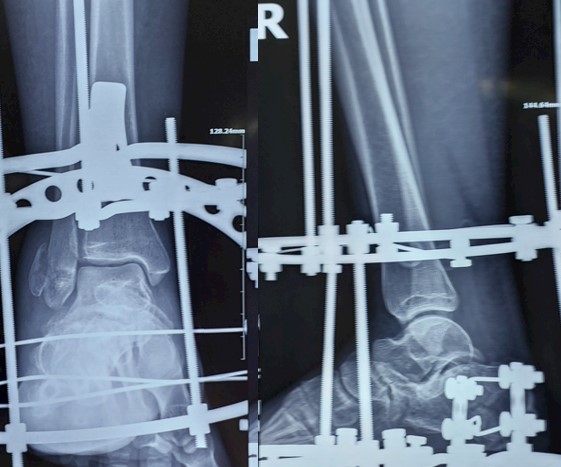

Зовнішня фіксація — це тимчасова міра, коли мʼякі тканини настільки пошкоджені, що будь-який розріз призведе до катастрофи. Металеві спиці пронизують кістку вище і нижче перелому, зʼєднані зовні рамою. Це конструкція, що тримає все на місці, дозволяючи набряку спасти, ранам загоїтись, а тоді — або фінальна операція та репозиція, або гіпс та консервативне лікування.